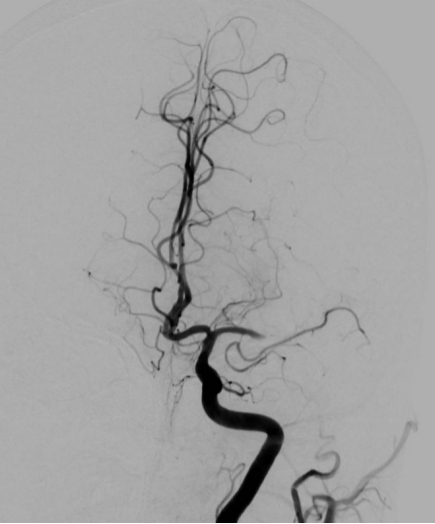

脑血管造影是目前脑血管检查的金标准,是通过动脉插管,使用造影剂显影完成脑血管检查的一种微创方法。其特点:简单、方便、安全、准确、创伤小。我院从2009年开始开展脑血管造影检查,目前开展经桡动脉、股动脉两种路径完成脑血管造影及治疗,桡动脉路径大大减轻患者的痛苦。目前开展的治疗手术:颅内外血管球囊扩张成形术、支架置入术、动脉瘤栓塞术、急症溶栓、取栓术,对于出血性脑血管病患者开展了微创血肿清除术。每年造影检查量约500例左右,治疗量约100例左右。介入技术水平走在了全市前列,取得了广大患者的好评。

图片1.jpg  图片2.jpg

经股动脉入路造影                                                               经桡动脉入路造影